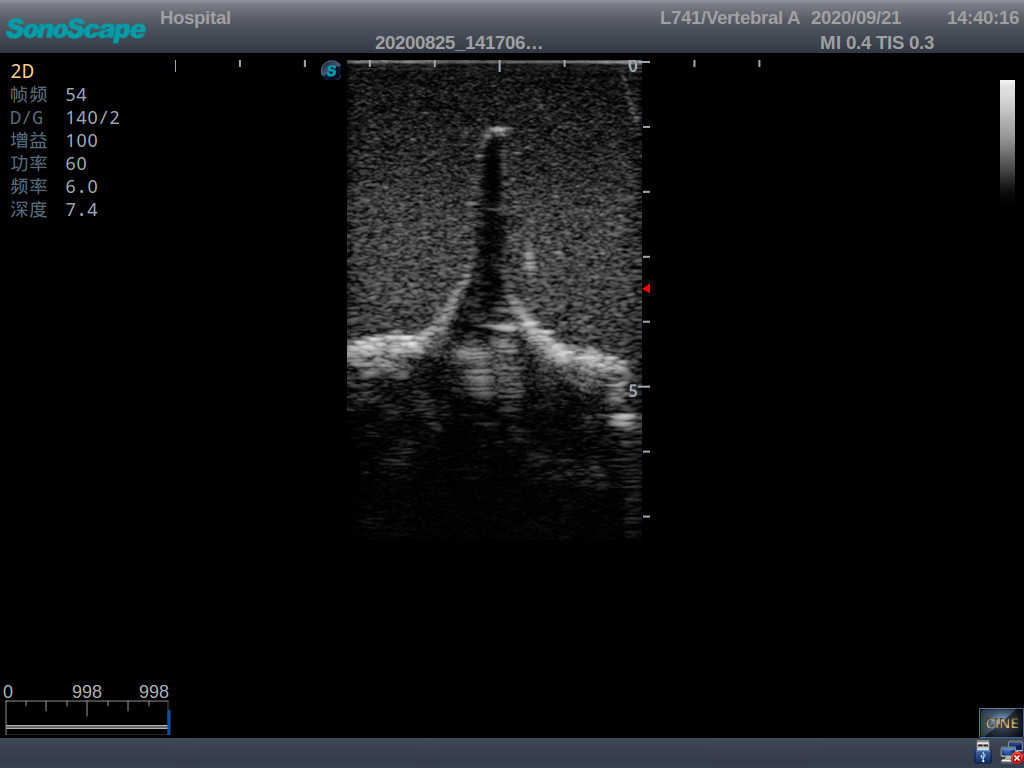

Model TYE1549.2

This model is an ideal choice for ultrasound-guided adult lumbar puncture training with true-to-life skin feel and touch, accurate anatomical structures as well as real clinical ultrasound images. Realistic resistance to needle tips and correct landmarks provide excellent hands-on experience.

· Realism:

1)  Advanced material for true-to-life skin touch, feel and puncture

2)  Real clinical ultrasound images

3)  Compatible with various real ultrasound machines

1)   Ultrasound-guided lumbar puncture practice